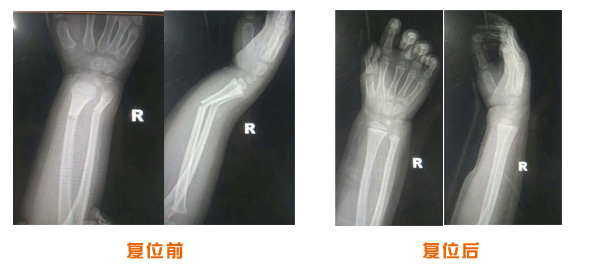

肥城市安駕莊梁氏骨科醫(yī)院是一所以梁氏手法正骨配合膏藥為特色的現(xiàn)代化專科醫(yī)院。

梁氏骨科術(shù)始創(chuàng)于清雍正年間,歷經(jīng)八代,至今已有三百年歷史。據(jù)1929年泰安縣志載“梁瑞圖先生,字增生,號蓮峰,安駕莊人,精岐黃并發(fā)明接骨,凡跌打車凡跌打車軋皮不破而碎骨者......【詳細(xì)】 |